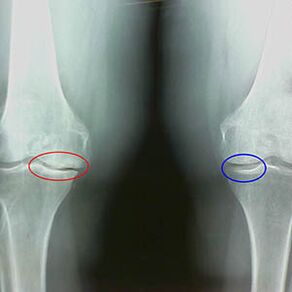

Merkmale x -art Ankunft der zweiten Kniephase illegal:

- Die spitzen Kanten der Inter -Script -Tuberkeln auf der Tibia, an denen das Kreuz -verdrängte Band befestigt ist;

- Verengung der gemeinsamen Lücke auf der medialen Seite;

- Die spitzen Kanten von Knochen -Kondyli auf den medialen Seiten, weniger häufig in lateral, abhängig von der Entwicklung der Valgus- oder Varor -Gelenkdeformation.

Für die zweite Phase von Larsen Die Verengung der gemeinsamen Lücke von über 50% ist charakteristischDies kann jedoch nur in Dynamik oder Vergleich mit einem anderen Gelenk kontrolliert werden.